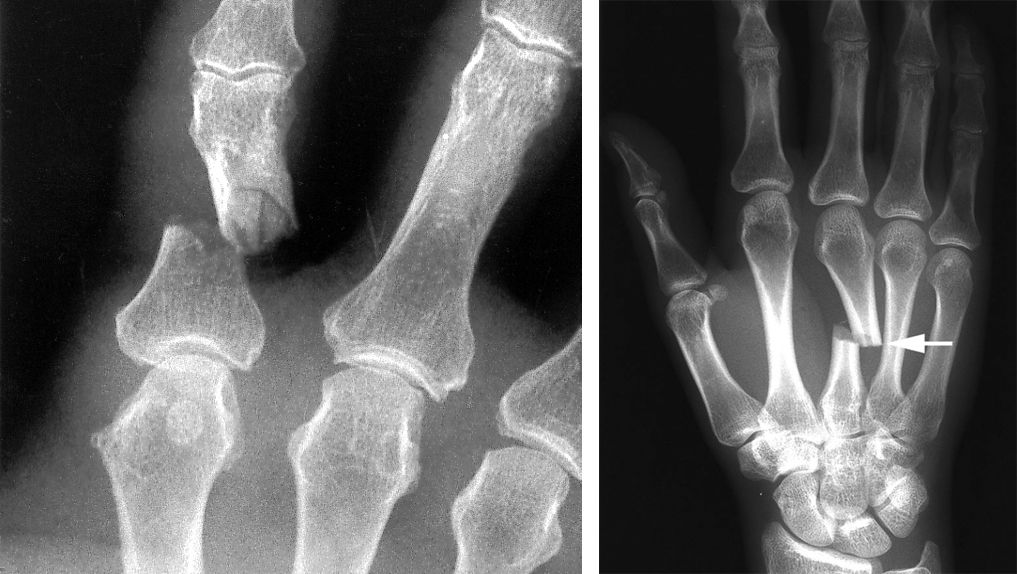

Phalanx fracture and metacarpal fracture

X-rays show a phalanx fracture (left) and a metacarpal fracture (right).

(Left) Reproduced from Kozin SH, Thoder JJ, Lieberman G: Operative Treatment of Metacarpal and Phalangeal Shaft Fractures. J Am Acad Orthop Surg 2000;8:111-121. (Right) Reproduced from Johnson TR, Steinbach LS (eds): Essentials of Musculoskeletal Imaging. Rosemont, IL American Academy of Orthopaedic Surgeons, 2004, p. 347.